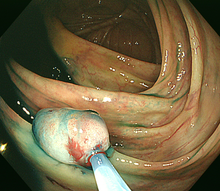

図 大腸がん

大腸癌の肉眼型

大腸癌は見た目の形(肉眼形態)により,0型-4型に分類されています。0型(表在型)は早期がんで、1-4型は進行がんに分類されます。